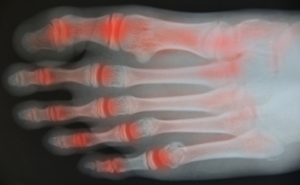

Toe arthritis is a condition where the joints in the toes become inflamed, causing pain and stiffness. The most common cause is osteoarthritis, which occurs as the cartilage in the toe joints wears down over time, often due to age or repetitive stress. Other causes include rheumatoid arthritis or injury to the toe. Symptoms of toe arthritis include pain in the affected joint, particularly during movement, swelling, and a reduced range of motion. In some cases, the joint may become deformed or misaligned. Relief from toe arthritis involves wearing proper footwear that provides support and cushioning, as well as anti-inflammatory medications to reduce pain and swelling. Specific exercises can also help improve joint flexibility and strength. In severe cases, surgical options may be considered to restore function and alleviate pain. If you have symptoms of arthritis in your toes, it is suggested that you consult a podiatrist who can offer you effective relief and management tips.

Arthritis is a joint disorder that involves the inflammation of different joints in your body, such as those in your feet. Arthritis is often caused by a degenerative joint disease and causes mild to severe pain in all affected areas. In addition to this, swelling and stiffness in the affected joints can also be a common symptom of arthritis.